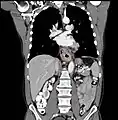

Additional testing is needed to assess how much the cancer has spread (see § Staging, below). Computed tomography (CT) of the chest, abdomen and pelvis can evaluate whether the cancer has spread to adjacent tissues or distant organs (especially liver and lymph nodes). The sensitivity of a CT scan is limited by its ability to detect masses (e.g. enlarged lymph nodes or involved organs) generally larger than 1 cm.[43][44] Positron emission tomography is also used to estimate the extent of the disease and is regarded as more precise than CT alone.[45] PET/MR as a novel modality has shown promising results in preoperative staging with fair feasibility and good correlation in comparison to PET/CT. It can enhance tissue differentiation with lowering the radiation dose to the patient.[46] Esophageal endoscopic ultrasound can provide staging information regarding the level of tumor invasion, and possible spread to regional lymph nodes.

Contrast CT scan showing an esophageal tumor (axial view)

Contrast CT scan showing an esophageal tumor (coronal view)